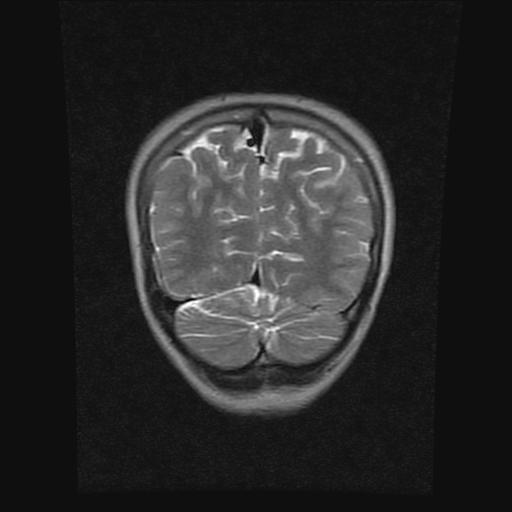

9岁女孩,三岁时诊断为癫痫,一直服丙戊酸钠,现患者一般情况良好,家长复查核磁片,看能否停药..

巨脑回

停药要结合临床,如无发作可以停。

停药要结合临床,如无发作可以停